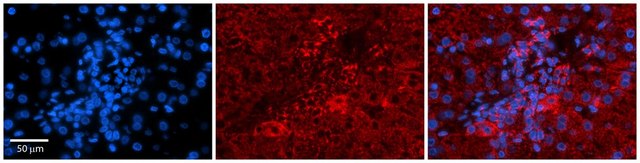

SAB2108198

Anti-PDGFB antibody produced in rabbit

Application:

IHC

immunoblotting: suitable, immunohistochemistry: suitable

Synthetic peptide directed towards the N terminal region of human PDGFB

Synthetic peptide located within the following region: NRCWALFLSLCCYLRLVSAEGDPIPEELYEMLSDHSIRSFDDLQRLLHGD